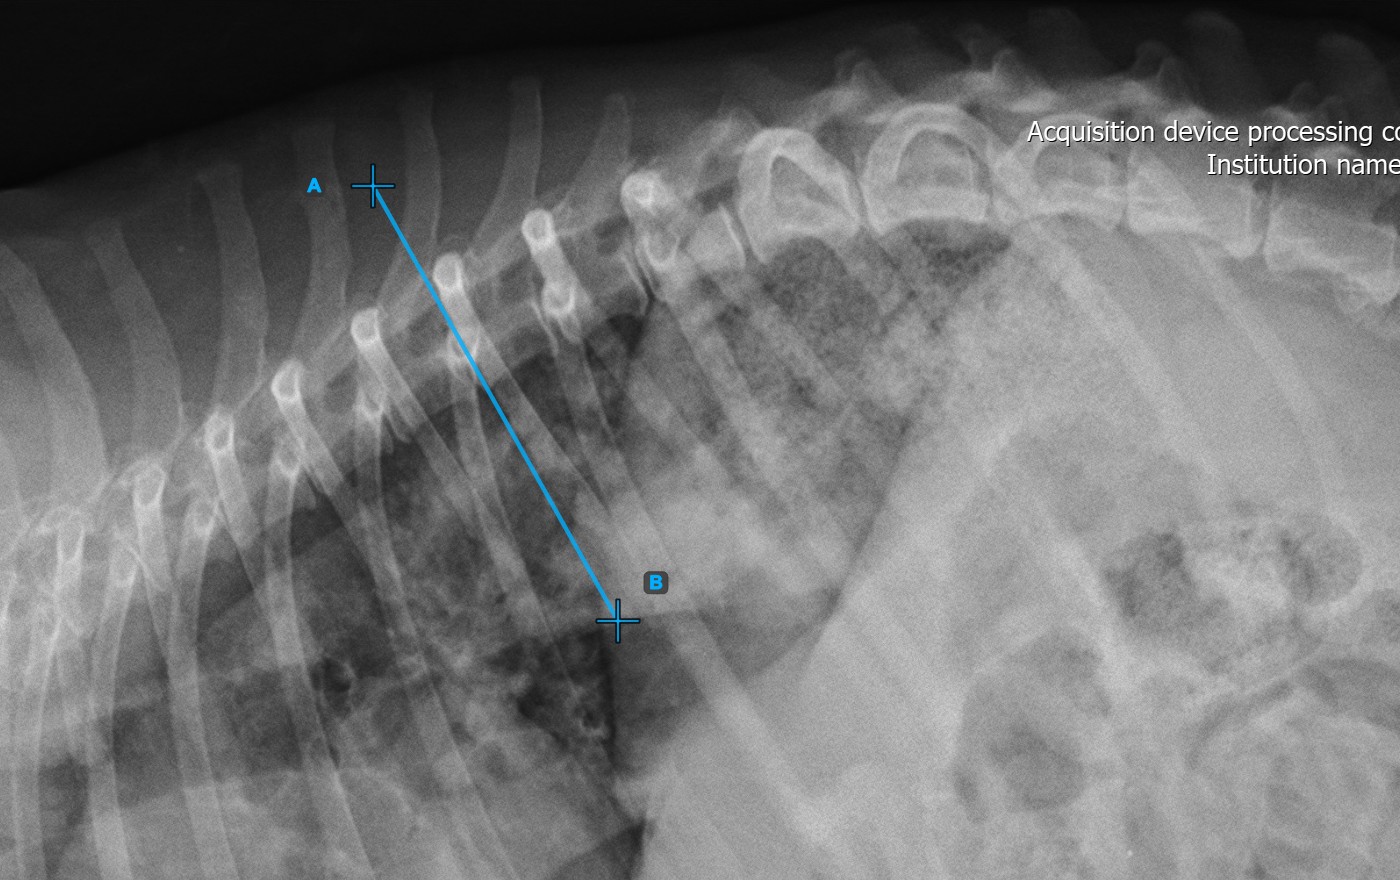

Kezdje el a mérést az első csigolya vonalának megjelölésével a gerincen.

Azonosítsa a csigolya véglemezt a gerinc legnagyobb görbületi deformitásának kezdőpontjánál. Helyezze el az első csigolya vonalának kezdő- és végpontját pontosan a meghatározott véglemezen. Szükség esetén igazítsa a pontokat a jeleneten, hogy a vonal jobban illeszkedjen a véglemezhez.

A lenti kép az első csigolya vonal tipikus elhelyezkedését ábrázolja.

../../_images/image373.jpg